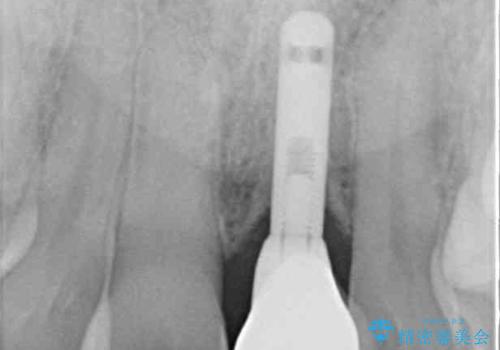

- 数年前に遠方の歯科医院で埋入したインプラントに、セラミッククラウンを装着したいとのことで来院された患者様です。

当院でも扱っているメーカーのインプラントであったため、土台を取り付ける手術とセラミッククラウンの装着を行うこととしました。

インプラントが唇側に埋入されており、セラミッククラウンの歯肉ラインが左右非対称となっていました。